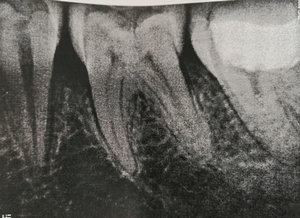

Около 3-х лет назад мне удалили нервы из верхней правой шестерки. Спустя 2 года воспалились корни, т.е. около 9 месяцев назад перелечивали корни, поставили коронку. Месяц назад зуб снова заболел, оказалось воспаление под корнем.

Хотелось бы узнать, действительно ли есть воспаление? И вообще в целом ситуацию насчет этого зуба, какое лечение следует предпринять? Есть 2 панорамных снимка.

Действительно, в зубе имеется хронический воспалительный процесс, причина — некачественное лечение каналов. Зуб будет лечиться в несколько посещений, и при квалифицированном подходе его вполне можно спасти.